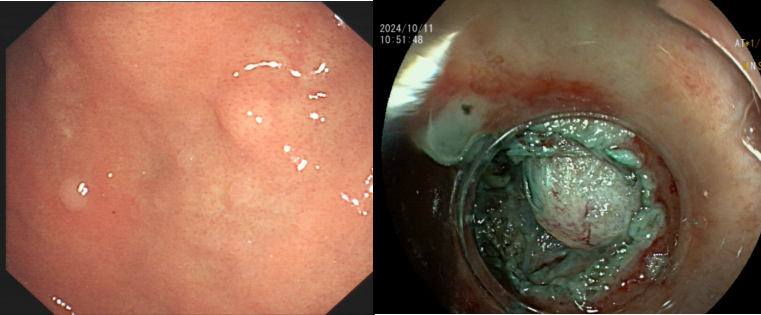

患者杨某,60岁女性,因腹胀痛2周行胃镜检查发现胃底肿物;患者唐某,56岁女性,因剑突下闷胀1年行胃镜检查发现胃底肿物。两个肿物经超声内镜下进一步探查, 均起源于固有肌层,且往腔外生长,消化内科副主任戴劲查看患者后,决定对其实施内镜下全层切除术(Endoscopic Full Thickness Resection,EFTR)。在对患者实施气管插管全麻后,首先用对病灶周围精准定位,随后操作高频电刀胃壁全层,进行主动穿孔,再逐步剥离直至完整切除瘤体。

切除肿瘤后,更加艰巨的挑战随之而来。消化内科主任戴劲介绍说:“瘤体切除后的胃壁穿孔,内镜下缝合起来困难重重,特别考验主刀医生的耐力和技术水平。”面对难题,他沉着冷静地用钛夹装置成功修补胃壁穿孔。患者术后病情平稳,无出血、感染等并发症,术后病理及免疫组化诊断为胃间质瘤。经过几天的观察,目前患者已顺利康复出院。

病例一

病例二